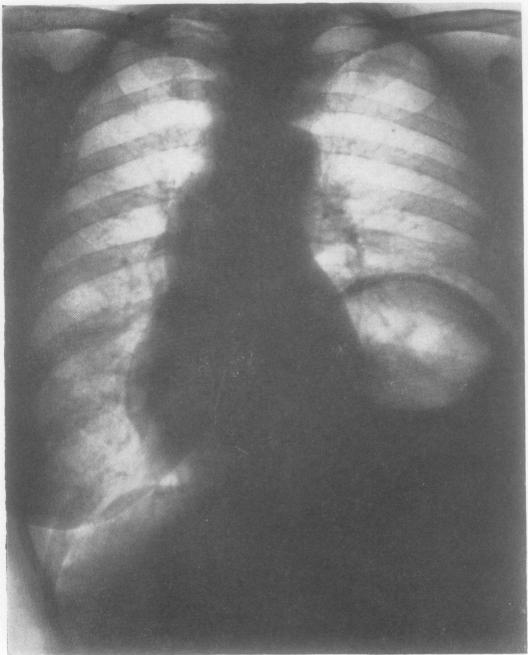

Fifty-seven cases of diaphragmatic hernia and eventration.

Thorax. 1950 Dec;5(4):343-61. doi: 10.1136/thx.5.4.343.